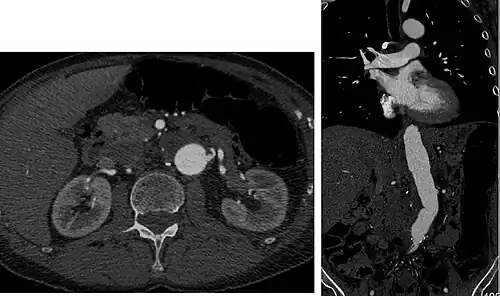

Aorta and great arteries

CTA can be used in the chest and abdomen to identify aneurysms in the aorta or other major blood vessels. These areas of weakened blood vessel walls that bulge out can life-threatening if they rupture. CTA is the test of choice when assessing aneurysm before and after endovascular stenting due to the ability to detect calcium within the wall.[3] Another positive of CTA in abdominal aortic aneurysm assessment is that it allows for better estimation of blood vessel dilation and can better detect blood clots compared to standard angiography.[4]

CTA is used also to identify arterial dissection, including aortic dissection in the aorta or its major branches. Arterial dissection is when the layers of the artery wall peel away from each other; this causes pain and can be life-threatening. CTA is a quick and non-invasive method of identifying dissections and can show the extent of the disease and if there is leakage.[4]